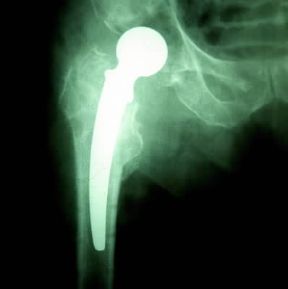

Protesi. Immagine radiografica dell'anca dopo la sostituzione.

De Agostini Picture Library

Le protesi interne passive sono costituite da tessuti di sostituzione di quelli naturali: vi sono ossa artificiali, usate normalmente per sostituire parti lese o asportate della scatola cranica e per l'attacco del femore; protesi mammarie in gel di silicone e in olio di soia che, inserite per via ascellare o attraverso una piccola incisione nella parete inferiore dell'areola, aumentano il volume del seno o ricostruiscono la mammella asportata con un intervento chirurgico. Vi sono inoltre vasi artificiali e valvole cardiache artificiali. Queste ultime, pur essendo passive, cioè non dotate di una dinamica propria, compiono un'importante interazione con il sangue permettendo un corretto pompaggio da parte dei ventricoli cardiaci. Se ne distinguono essenzialmente due tipi: quelle sintetiche, metalliche,dotate di notevole resistenza e durevolezza, ma che richiedono una terapia anticoagulante per la tendenza del materiale a formare trombi sanguigni, e quelle cosiddette biologiche derivate da tessuti animali (di suino o bovino) che non necessitano di terapia anticoagulante ma che non danno sufficienti garanzie per quanto riguarda la durata. Come per quelle cardiache, esistono protesi vascolari biologiche e sintetiche; le prime possono essere a loro volta distinte in autologhe (dello stesso individuo), omologhe (per esempio vene prelevate da cadavere) ed eterologhe (di bovino). Le più usate sono le autologhe (soprattutto la safena) perché resistenti alle trombosi e alle infezioni ed esenti da problemi di ordine immunitario (rigetto). Le protesi sintetiche sono realizzate con materiali come il dacron e il politetrafluoroetilene espanso che costituiscono l'impalcatura sulla quale, durante i primi mesi dal trapianto, si forma il rivestimento naturale dell'arteria fatto di cellule, fibrina e collagene. L'impianto di queste protesi può provocare l'insorgenza di un'infezione che può attecchire sul materiale non biologico richiedendone la pronta asportazione chirurgica. § Le protesi interne attive sono quelle più complesse in quanto assommano i problemi sia di tollerabilità dei materiali sia di autonomia di funzionamento (vedi pace-maker e cuore artificiale).